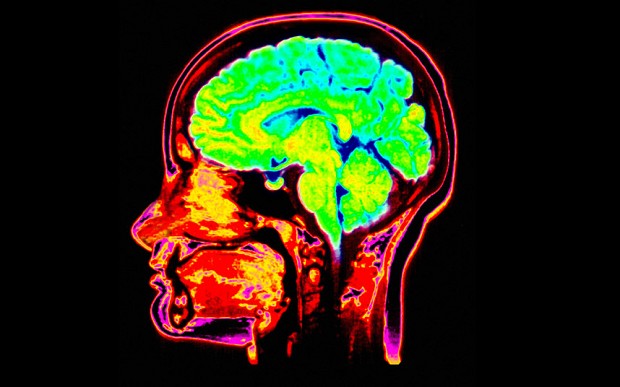

A légszennyezés növeli az agyvérzés kockázatát – derült ki egy világméretű kutatásból, amelyről a The Guardian online kiadása számolt be.

A The Lancet Neurology című folyóiratban ismertetett eredmények a téma szakértői szerint azért riasztóak, mert megmutatják, hogy eddig alábecsülték a légszennyezés tüdőre, szívre és agyra gyakorolt hatását.

A légszennyezés 17, a háztartás levegőjének minősége 16 százalékot jelentett a stroke-tényezők között. Hosszú távon a szennyezett levegő úgy fokozhatja a stroke kockázatát, hogy megvastagítja az agyi erek falát, ezzel a vér sűrűbb lesz, a vérnyomás emelkedik, növekszik a vérrögök kialakulásának esélye.